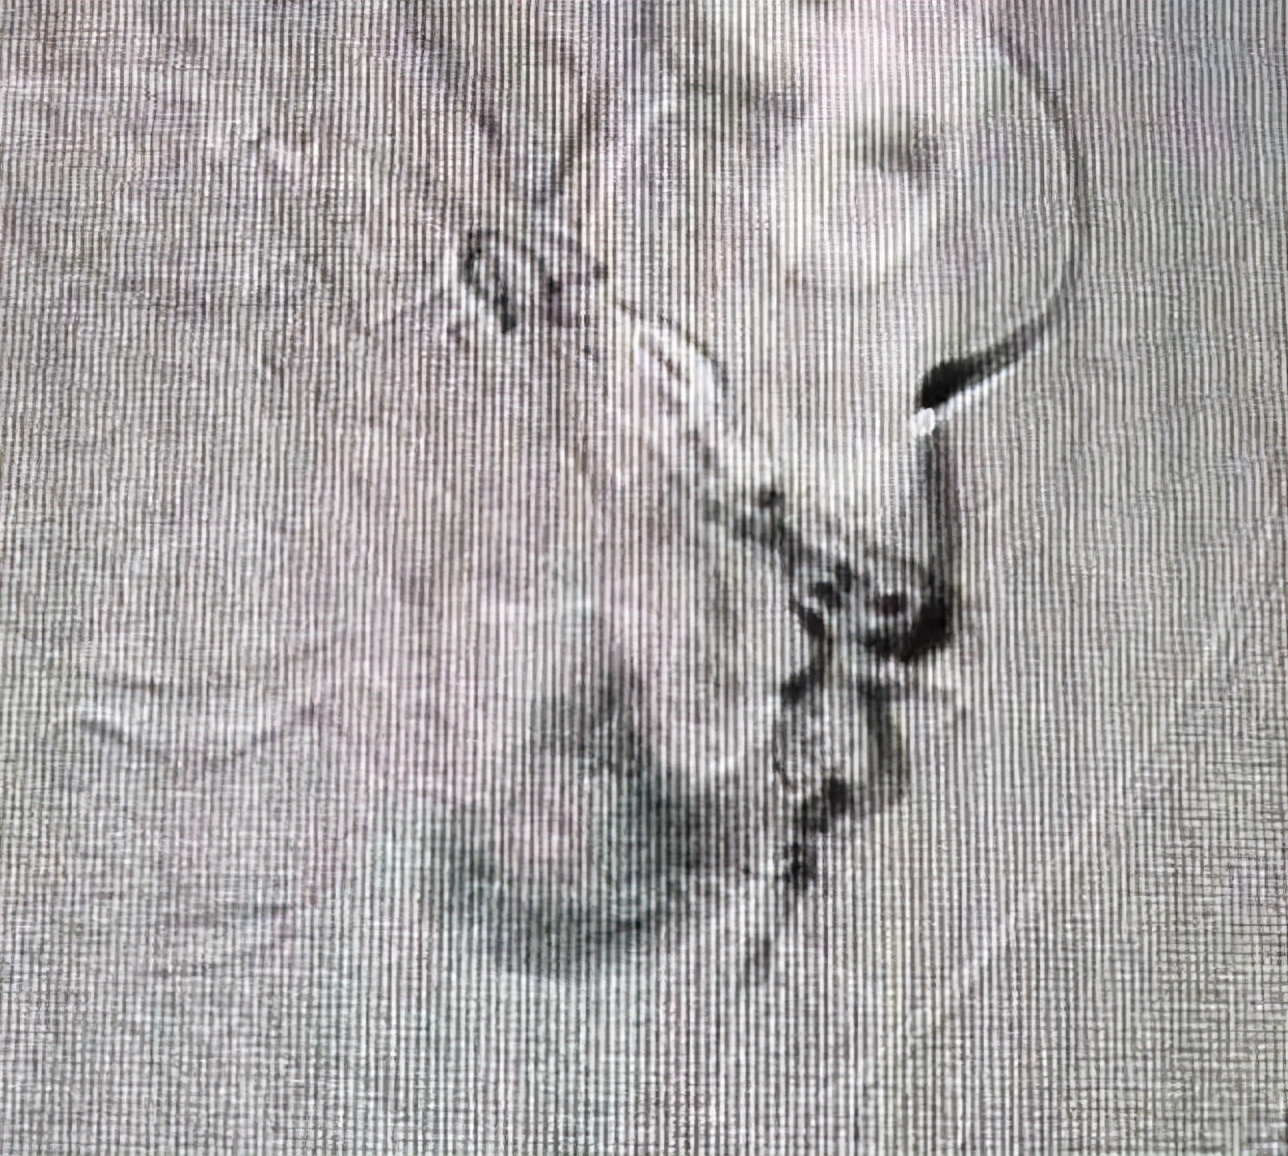

DSA下造影,找到肿瘤供血血管、可见肿瘤形态、大小。

手术方案:将化疗药直接通过导管注入到肿瘤内,之后用栓塞颗粒栓塞血管,遏制肿瘤供血血管。